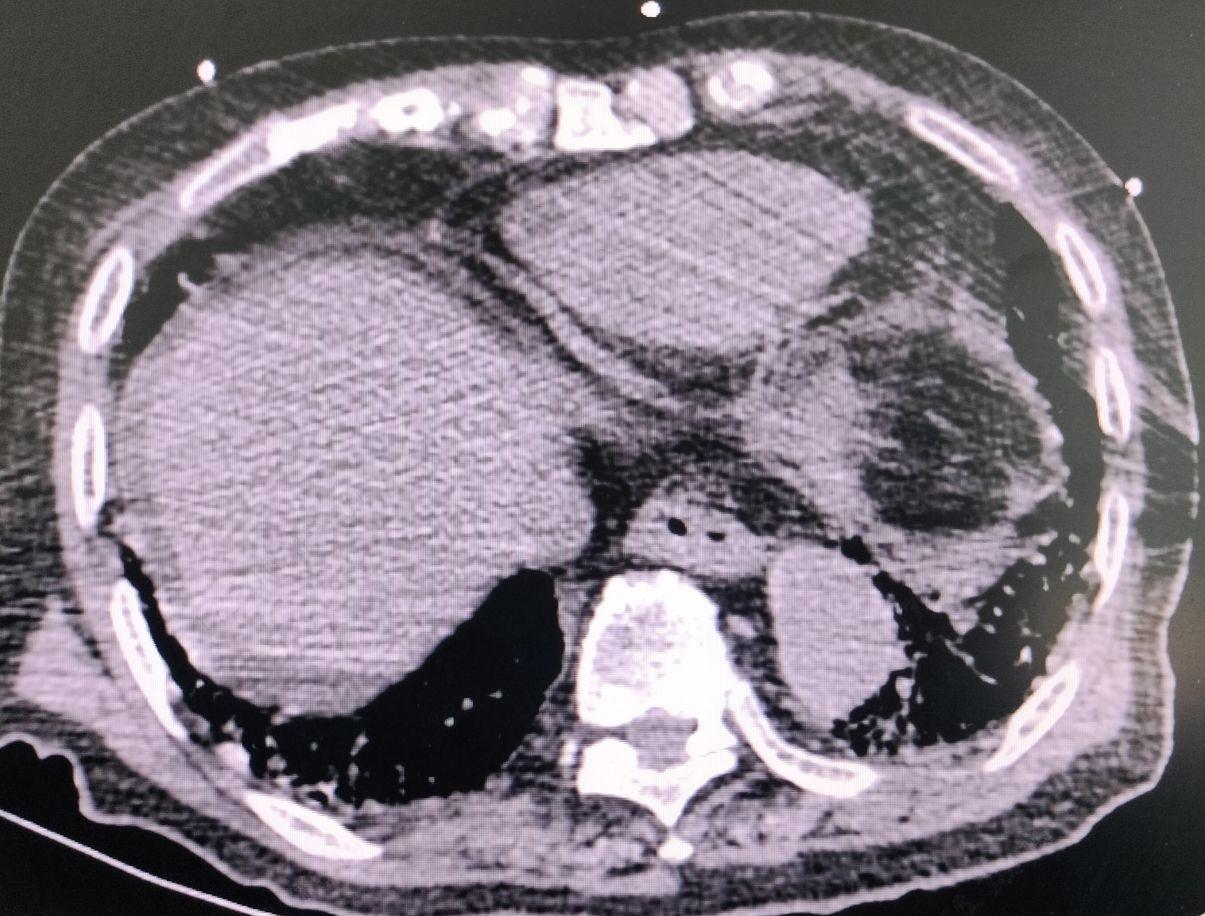

胸腹部CT平扫+增强示:1.两肺结节。2.符合慢支、肺气肿改变;两肺感染。3.双侧胸腔少量积液。4.升主动脉增宽,心影增大,心包少量积液,胸主动脉、冠脉钙化灶;左侧第2前肋骨折可疑,建议3-4周后复查。5.肝右叶片状静脉期、延时期强化灶,考虑异常灌注。6.膈下少许游离气体影,考虑消化道穿孔伴腹膜炎改变。7.结肠肝曲占位,考虑 Ca伴周围侵犯,周围稍大淋巴结。8.前列腺结节状强化灶,考虑前列腺增生。9.肝囊肿;胆囊多发结石;双肾囊肿。10.腹腔、盆腔积液;双侧腹股沟疝。

3.辅助检查:CT平扫+增强示:1.两肺结节,拟低危,年度复查。2.符合慢支、肺气肿改变;两肺感染。3.双侧胸腔少量积液。4.膈下少许游离气体影,考虑消化道穿孔伴腹膜炎改变。5.结肠肝曲占位,考虑Ca伴周围侵犯。

患者高龄,男性,腹部剧痛急诊入院,查体腹部呈板状腹,压痛反跳痛阳性,腹部ct提示膈下见游离气体,诊断横结肠破裂穿孔明确,消化道穿孔患者常表现为突发剧烈腹痛,迅速蔓延至全腹,伴有明显腹膜刺激征(压痛、反跳痛、肌紧张)。因穿孔继发脓毒血症,可出现高热、寒战、心动过速、呼吸急促、低血压、意识改变等感染性休克表现。

诊断要点1. 病史与体征:结肠癌病史或相关症状(如排便习惯改变、便血),突发急性弥漫性腹膜炎体征,2. 影像学检查:腹部CT平扫+增强是首选,可显示横结肠肿瘤、腹腔游离气体、肠管穿孔征象及腹腔积液。3. 实验室检查:白细胞显著升高或降低,降钙素原(PCT)、C反应蛋白(CRP)急剧升高,血培养可能阳性。4. 术中探查:是最终确诊手段,可见肿瘤及穿孔部位,腹腔内大量脓性渗液。